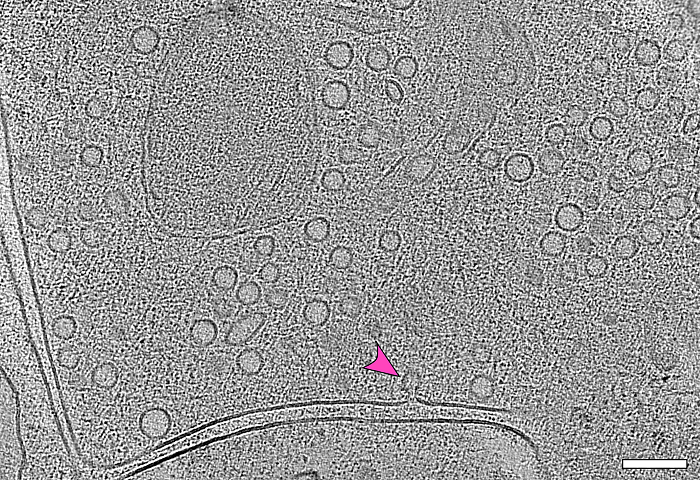

Das Bild zeigt den ultrakurzen Moment, in dem ein Vesikel (Pfeil) mit der Zellmembran fusioniert. Durch die Überlagerung mehrerer elektronenmikroskopischer Bilder – die Elektronentomographie – wird sichtbar, wie viele Vesikel am Ende einer Nervenzelle darauf warten, ihre Botenstoffe in den synaptischen Spalt abzugeben. Dieser Zwischenraum zwischen zwei Nervenzellen ist in der Aufnahme, die in der CFcryo-EM (Core Facility for cryo-Electron Microscopy) entstanden ist, als doppelte Linie zu erkennen. © Jana Kroll Charité/Max Delbrück Center

Der Vorgang dauert nur wenige Millisekunden: Ein Vesikel, gefüllt mit Neurotransmittern und nur ein paar Nanometer groß, nähert sich der Zellmembran, verschmilzt mit ihr und gibt seine Botenstoffe an den synaptischen Spalt ab – sodass sie sich dort an die nächste Nervenzelle heften können. Ein Team um Professor Christian Rosenmund von der Charité – Universitätsmedizin Berlin hat diesen für die Arbeit des Gehirns entscheidenden Moment in mikroskopischen Bildern festgehalten. Wie sie das geschafft haben, beschreiben die Berliner Forschenden im Fachblatt „Nature Communications“.

„Niemand wusste bisher, wie die Fusion der synaptischen Vesikel mit der Zellmembran im Detail abläuft“, sagt die Erstautorin der Studie, Dr. Jana Kroll, die mittlerweile in der Arbeitsgruppe „Strukturbiologie Membran-assoziierter Prozesse“ von Professor Oliver Daumke am Max Delbrück Center forscht. „In unseren Experimenten mit Mäuse-Neuronen konnten wir zeigen, dass sich zunächst eine punktförmige Verbindung bildet. Dieser winzige Stiel erweitert sich dann zu einer Pore, durch die die Neurotransmitter in den synaptischen Spalt gelangen“, erläutert Kroll.

Dabei stießen die Forschenden auf ein weiteres interessantes Detail: „Wir konnten erkennen, dass die meisten der fusionierenden Vesikel über kleine Filamente mit mindestens einem weiteren Vesikel verbunden sind – sobald ein Vesikel mit der Zellmembran verschmilzt, steht schon das nächste bereit“, berichtet Kroll. „Wir gehen davon aus, dass diese direkte Form der Vesikel-Rekrutierung es ermöglicht, dass Neurone auch über einen längeren Zeitraum hinweg Signale senden und so ihre Kommunikation aufrechterhalten können.“